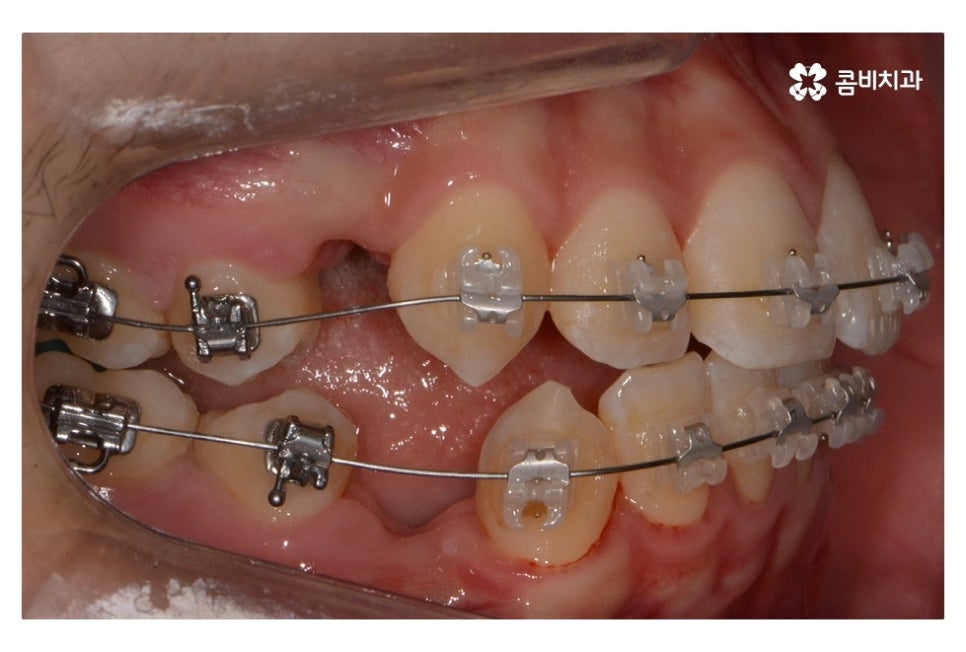

오늘 보여드릴 중학생치아교정 사례의 경우에는

악골의 위치는 정상적인 상태에서 불규칙한 치열로 인해

교정 치료를 진행한 사례라고 할 수 있어요.

위 환자분의 경우 발치가 진행된 사례로 치아의 이동 공간을

고려할 때 발치가 필요했고 환자분도 보다 나은

심미성을 위해서 동의한 상황이라고 할 수 있어요.

위 사진에서 보시면 시간이 지나면서 발치를 했던 치아의

공간이 사라지고 교정을 통해서 치열이 가지런해진 것을 확인할 수 있는데요.